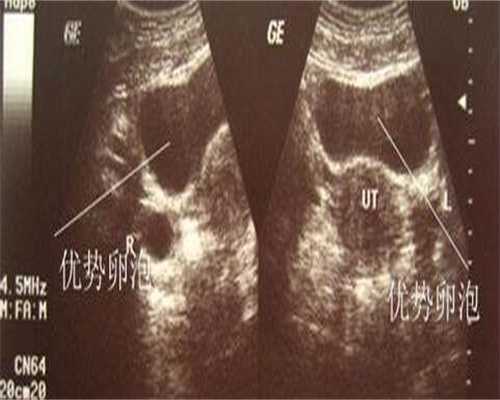

迫近排卵时正常成熟的优势卵泡的声像图具有以下特征:①卵泡最大直径达20mm,优势卵泡最大直径范围为17~24mm,体积2.5~8.5m13。直径小于17mm者为非成熟卵泡。②卵泡外形饱满呈圆形或椭圆形,内壁薄而清晰,或可见内壁卵丘所形成的一金字塔形的高回声,多在排卵前24~30小时易于显示。亦可见优势卵泡周围有一低回声晕(多由排卵前卵泡膜组织水肿所致)。③卵泡位置移向卵巢表面,且一侧无卵巢组织覆盖,并向外突出(图43—5)。